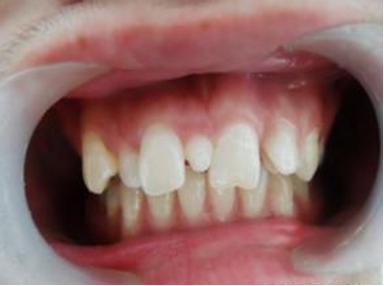

李奶奶的宝贝孙子六岁半了,上颌前面的两颗门牙已经替换了三个多月,可是两颗新牙间缝隙不见变小,反而越来越大了,远没有乳牙长得那么整齐,马上要上小学了,和其他孩子相比,门牙有大缝这事最近让李奶奶一直着急上火,平日总挂在脸上的笑容也不见了,今天一大早就带着孩子到口腔科检查。

儿童口腔科的医生经过专科查体并配合X线检查,发现是孩子的两颗新长门牙之间有一颗多生牙在作怪,这让李奶奶更紧张了。